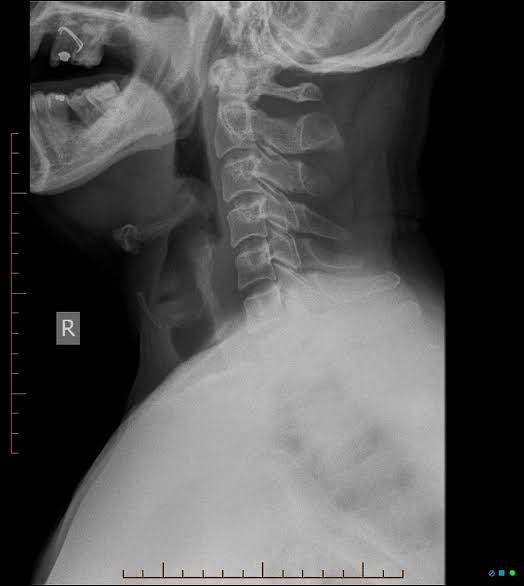

Epiglottitis

Epiglottitis is a potentially life-threatening condition that occurs when the epiglottis — a small cartilage "lid" that covers your windpipe — swells, blocking the flow of air into your lungs. A number of factors can cause the epiglottis to swell — burns from hot liquids, direct injury to your throat and various infections. The most common cause of epiglottitis in children in the past was infection with Haemophilus influenzae type b (Hib), the same bacterium that causes pneumonia, meningitis and infections in the bloodstream. Epiglottitis can occur at any age.